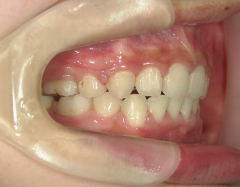

主訴:上の歯が前に出ている。

no.18_2196_治療前_右.jpgno.18_2196_治療前_正面.jpgno.18_2196_治療前_左.jpg

no.18_2196_治療後_右.jpgno.18_2196_治療後_正面.jpgno.18_2196_治療後_左.jpg